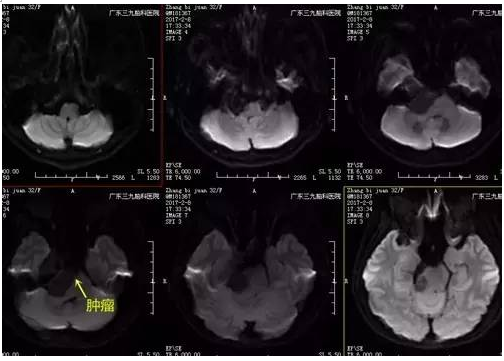

张女士,32岁,因右侧面部针刺样痛疼伴麻木持续2月余未有缓解,速来医院就诊,门诊CT提示右侧中后颅窝等密度影,收入住院治疗。入院后完善相关术前检查,术前DWI检查示右侧跨中后颅窝占位性病变呈低信号,术前磁共振示哑铃状病变,各序列以高信号为主高低混杂信号影,瘤体约4.5cm×3.7cm×3.3cm,完善检查后,行右侧中后颅窝占位性病变切除术,手术由神经一科主任张良主刀完成。术程顺利,术后患者恢复良好,未见并发症,术后MR提示肿瘤切除。